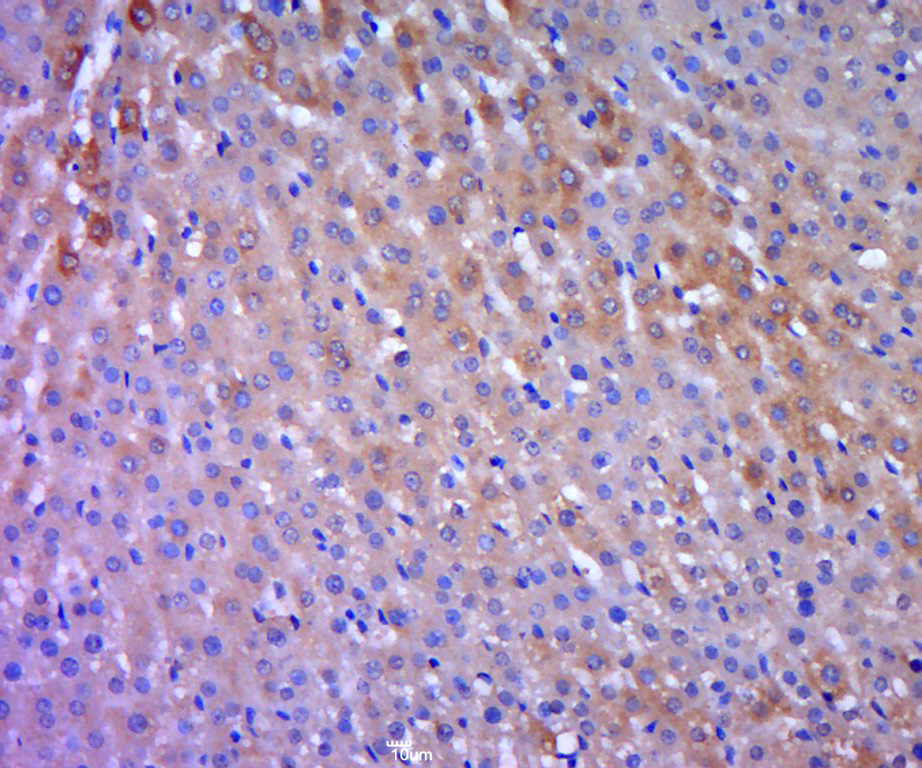

Paraformaldehyde-fixed, paraffin embedded (rat liver tissue); Antigen retrieval by boiling in sodium citrate buffer (pH6.0) for 15min; Block endogenous peroxidase by 3% hydrogen peroxide for 20 minutes; Blocking buffer (normal goat serum) at 37°C for 30min; Antibody incubation with (ODC) Polyclonal Antibody, Unconjugated (bs-1294R) at 1:400 overnight at 4°C, followed by a conjugated secondary (sp-0023) for 20 minutes and DAB staining.